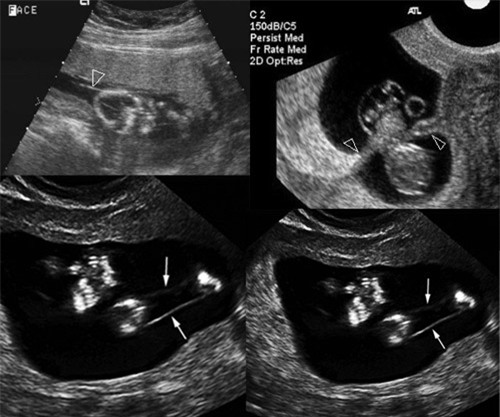

Hiện tượng dải sợi ối được phát hiện thông qua siêu âm. Những điểm có dải sợi ối được đánh dấu bằng mũi tên Hiện tượng dải sợi ối xác định bằng cách nào? Phát hiện mẹ bầu có bị dải sợi ối hay không là dựa vào siêu âm hình thái có thể thấy được em bé có bị dị tật hay không. Vì vậy, với những mẹ rơi vào trường hợp hợp này cần phải đi khám thai thường xuyên để được theo dõi kỹ lưỡng. Trên thế giới, các ca phẫu thuật cho thai nhi đã được tiến hành. Các chuyên gia sẽ mở tử cung của mẹ, làm các phẫu thuật thích hợp cho thai nhi rồi đặt bé trở lại trong tử cung và tiếp tục phát triển cho đến ngày chào đời. Đây cũng là hướng giải quyết cho những trường hợp dải sợi ối nghiêm trọng. Ngoài ra, với những dị tật do dải sợi ối như dính ngón tay, dính ngón chân, cụt ngón tay, chân khoèo, các bác sỹ có thể tiến hành các ca phẫu thuật chỉnh hình để khắc phục. |